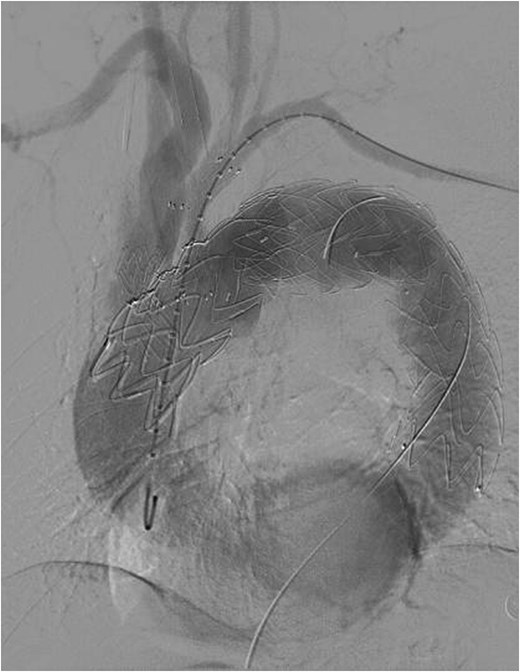

The patient underwent F/B TEVAR on August 17, 2022. Physician-modified stent-graft (PMSG) were deployed in all three branches of the arch. Aortic stent graft from Captivia, Medtronic, USA were utilized; Branch stent graft included iliac artery stent graft and coated stent graft, from Medtronic, BD, etc. Following stent graft placement, angiography revealed unobstructed flow in the three branches of the superior arch, and the arterial aneurysm disappeared completely (see Fig. 2). Due to the twisted aorta, the length of the aortic stent graft delivery system was insufficient, leading to the use of a common iliac artery-artificial vessel approach. The procedure was complicated by anastomosis rupture and massive hemorrhage, requiring a 1000 ml blood transfusion. Post-surgery, the patient was admitted to the intensive care unit and developed a high fever, significant hemoglobin drop, and unstable circulation. An urgent computed tomography revealed a retroperitoneal hematoma, which was removed on August 19, 2022. Intraoperative exploration uncovered a large number of blood clots, totaling ⁓1000 ml, with no obvious bleeding points found. The patient developed bacteremia, pulmonary infection, septic shock, acute kidney injury (KDIGO3 stage), and fungal infection. After long-term supportive treatment, the patient was transferred to a general ward on October 10, 2022, and discharged on October 28, 2022.

Despite recovery, the patient remained physically exhausted and required ongoing rehabilitation. In May 2023, after a COVID-19 infection, the patient experienced blood in phlegm. CTA confirmed successful aneurysm repair with no endoleak (Fig. 3). Thus the patient was hospitalized in the respiratory department. Relevant pulmonary examination indicators and lung CT results revealed no lung lesions associated with blood in sputum (Fig. 4). However, throughout July, 2023, intermittent blood in phlegm continued, and a CTA on July 19, 2023, revealed a type IV endoleak (Fig. 5). Conversely, aortography on July 27, 2023, showed no obvious endoleak. Closed drainage of the left thoracic cavity was performed, but blood in phlegm recurred on August 9, 2023. A Gore C-TAG stent graft was deployed in the thoracic aortic arch, with its proximal end anchored at the ostium of the left subclavian artery stent graft to ensure complete coverage of the endoleak site both proximally and distally(Fig. 6). Post-surgery, blood in phlegm symptoms abated.